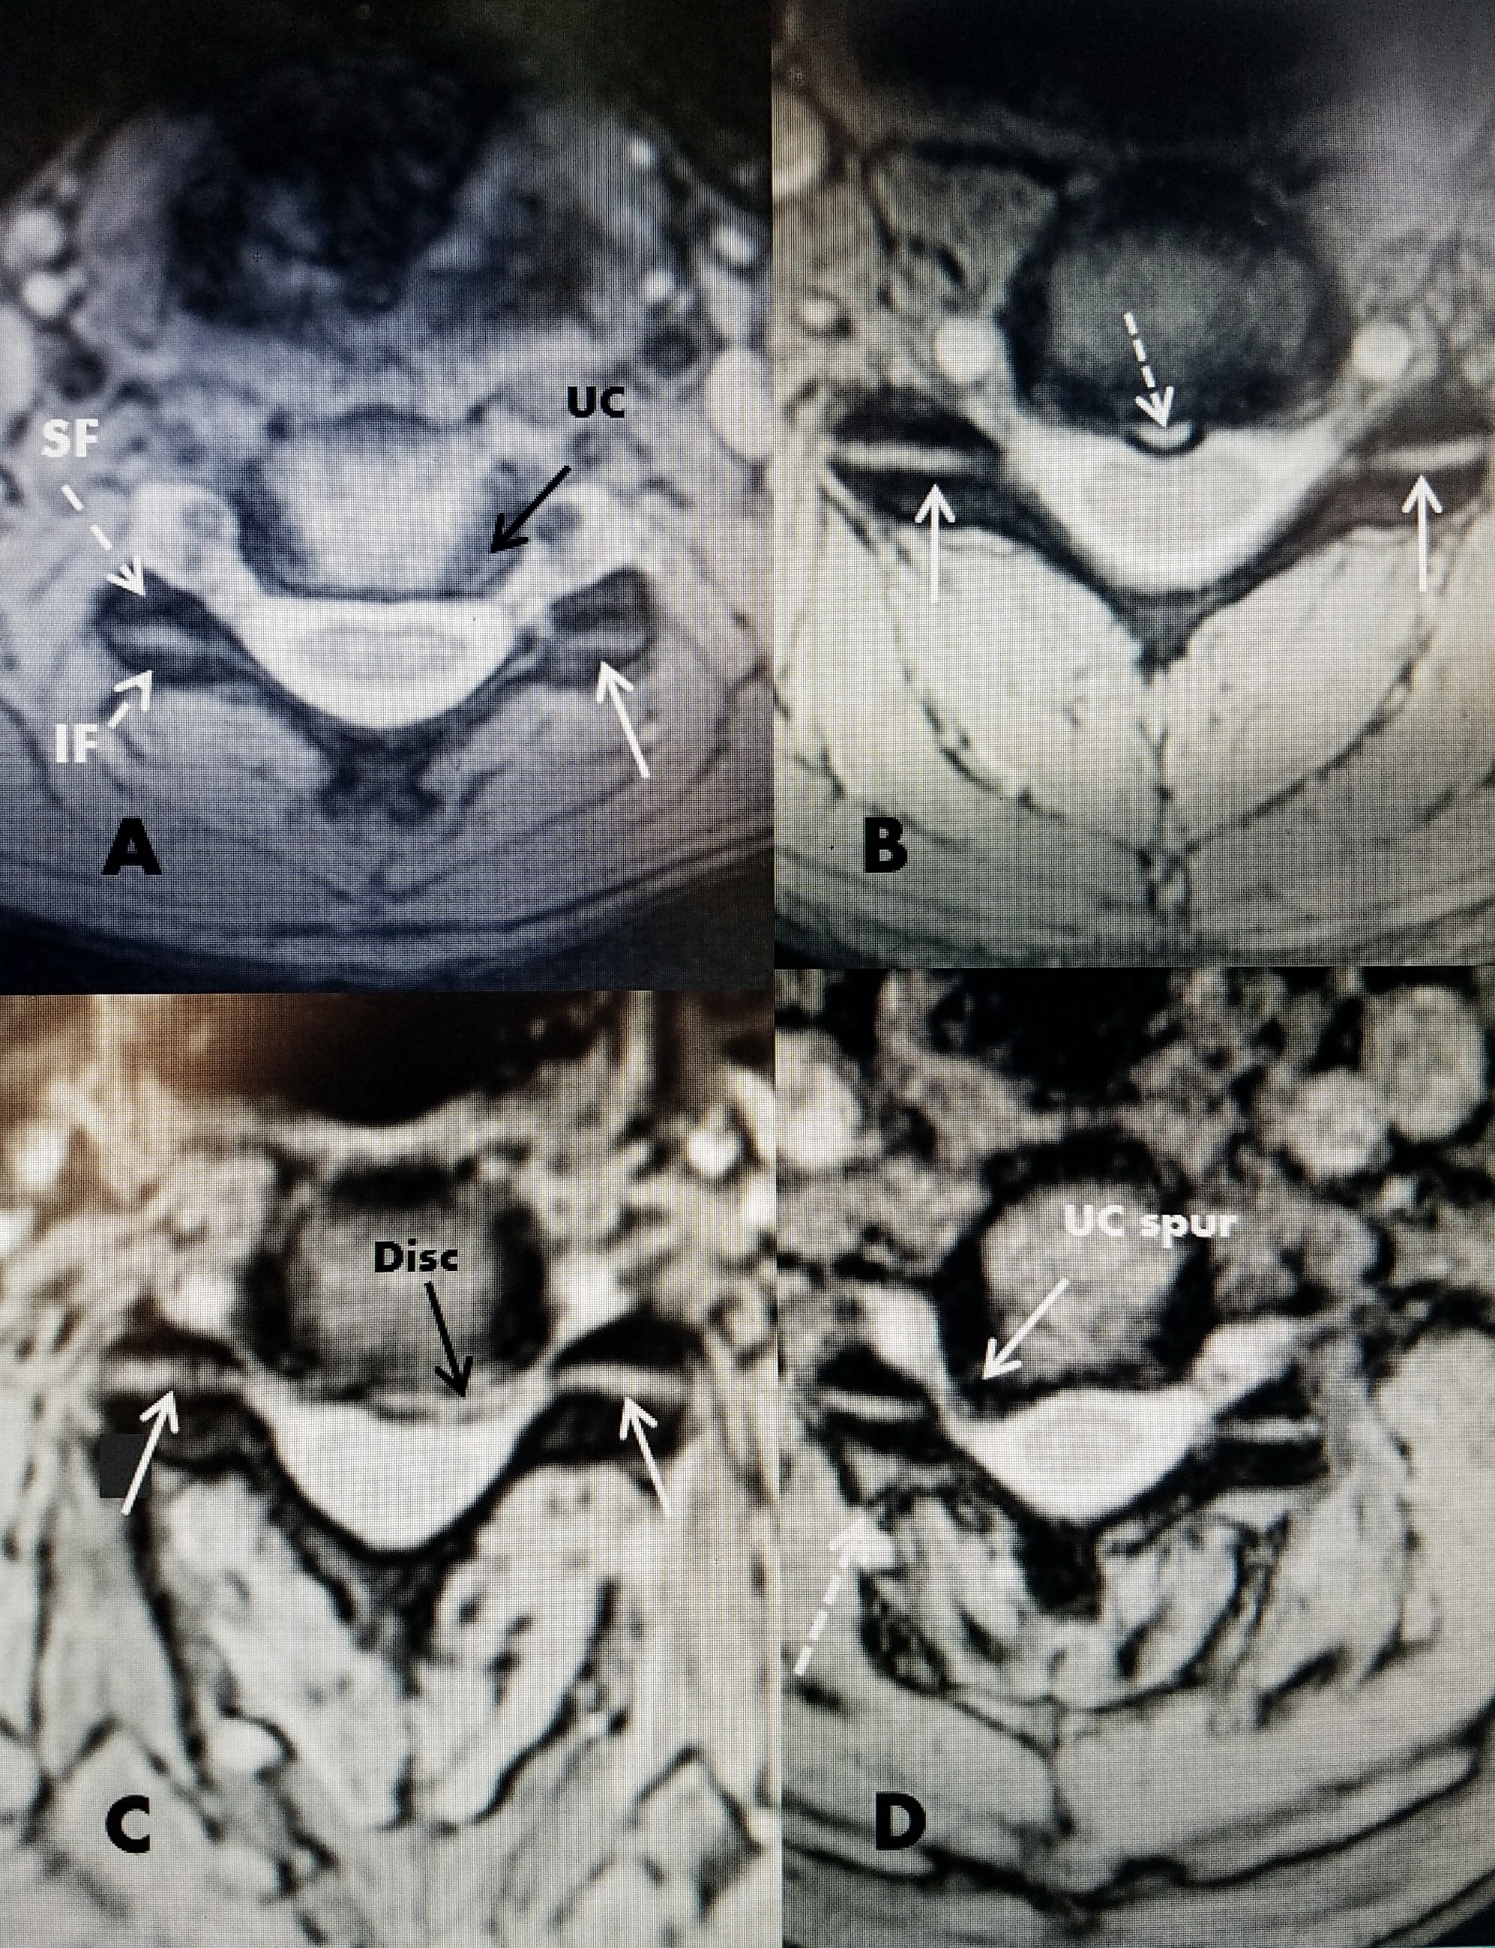

From www.researchgate.net

Anatomical orientation of a facet joint between two vertebrae Facet Joint Overgrowth Learn about the causes, symptoms, diagnosis, and treatment. Lumbar facet joint disorders most commonly cause. Web symptoms and diagnosis of facet joint disorders. This is a very common disease process (its prevalence increasing with age) and is a common source of disability with significant economic impact. Web facet arthritis is a condition that affects the joints in the spine, causing. Facet Joint Overgrowth.